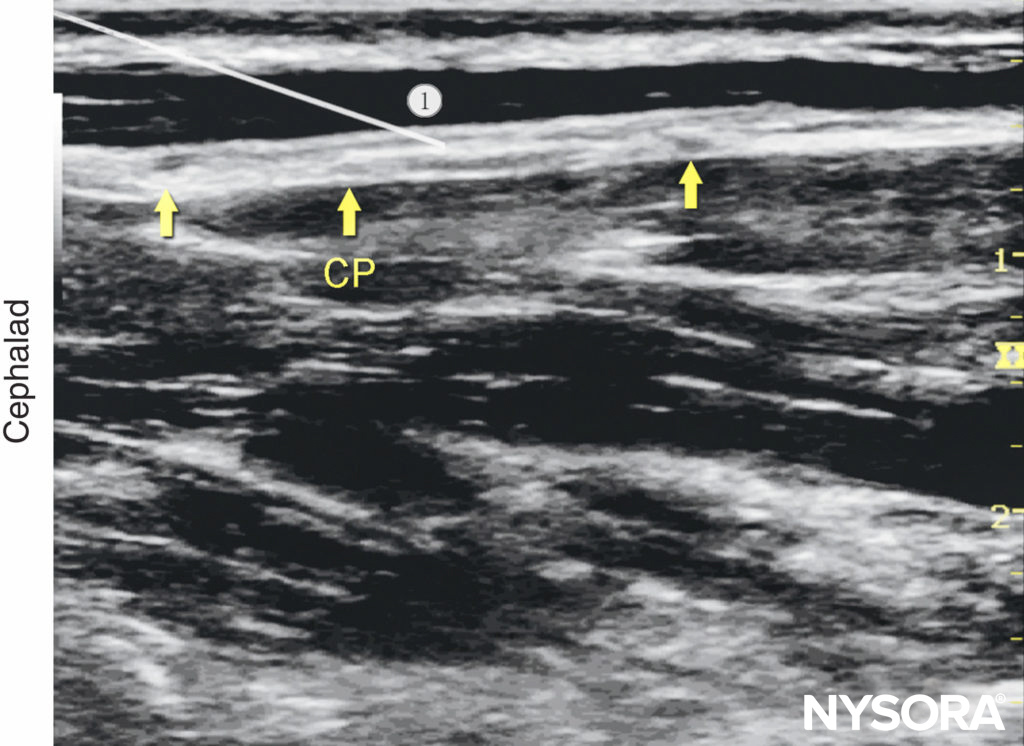

If the plexus is not visualized, an alternative sub sternocleidomastoid approach may be used. In this case, the needle is passed behind the SCM, and the tip is directed to lie in the space between the SCM and the prevertebral fascia, close to the posterior border of the SCM (Figures 7b, 10 and 11). Local anesthetic (5–15 mL) is administered and should be visualized layering out between the SCM and the underlying prevertebral fascia (Figure 12). If the injection of local anesthetic does not appear to result in an appropriate spread, needle repositioning and further injections may be necessary. Because the cervical plexus is made up of purely sensory nerves, high concentrations of local anesthetic are usually not required; ropivacaine 0.25–0.5%, bupivacaine 0.25%, or lidocaine 1% is a sufficient

Figure 11. Cervical plexus (longitudinal view): needle position to nerve block the cervical plexus (CP).